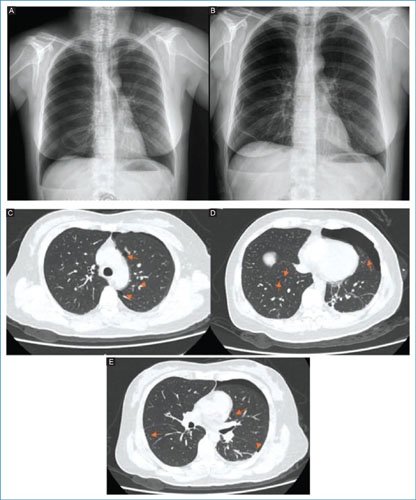

In January 2024, she presented a new episode of right pneumothorax, so she went to a private unit where a low-caliber pleural catheter was placed and chemical pleurodesis was performed without complications, with resolution of the condition. However, 3 months later, she presented a third right pneumothorax, which was the reason she came to our unit. She was again managed with a low-caliber pleural catheter, achieving resolution within 48 hours (Fig. 1A). The patient requested voluntary discharge after resolution of the condition; however, 13 days later she presented a new right pneumothorax (Fig. 1B). Given the recurrence, a low-caliber pleural catheter was placed to resolve the pneumothorax, and the patient was hospitalized with the aim of performing a diagnostic work-up due to the suspicion of probable lymphangioleiomyomatosis. Empirical treatment was initiated with sirolimus at a dose of 1 mg every 24 hours orally and budesonide/formoterol 160/4.5 µg inhaler (1 inhalation every 12 hours). Four days after admission, she developed a new right pneumothorax. A simple pulmonary computed tomography was requested, which revealed the presence of approximately 15 cystic formations at different levels (Figs. 1CE). Laboratory studies did not show relevant alterations to the case.

Figure 1. A: right spontaneous pneumothorax is observed. B: right pulmonary expansion with Heimlich valve catheter is highlighted. C: the presence of multiple pulmonary bullae is noted. D: presence of left pneumothorax with multiple bullae in both lungs. E: presence of bullae at the bilateral basal pulmonary level.